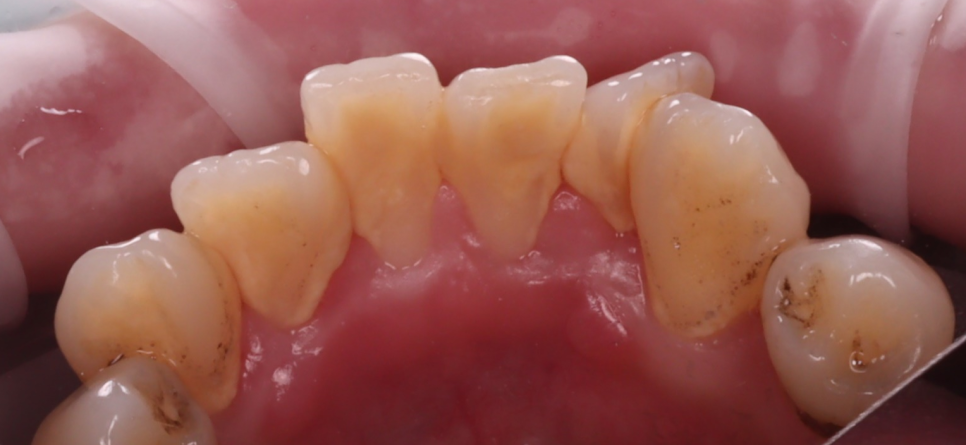

겉으로 보이는 표면에

착색이 도드라진 상태였고,

치아의 안쪽 면, 씹는 면 부근에

브라운 계열의 색소가 고착되어 있었습니다.

촬영일 : 250607